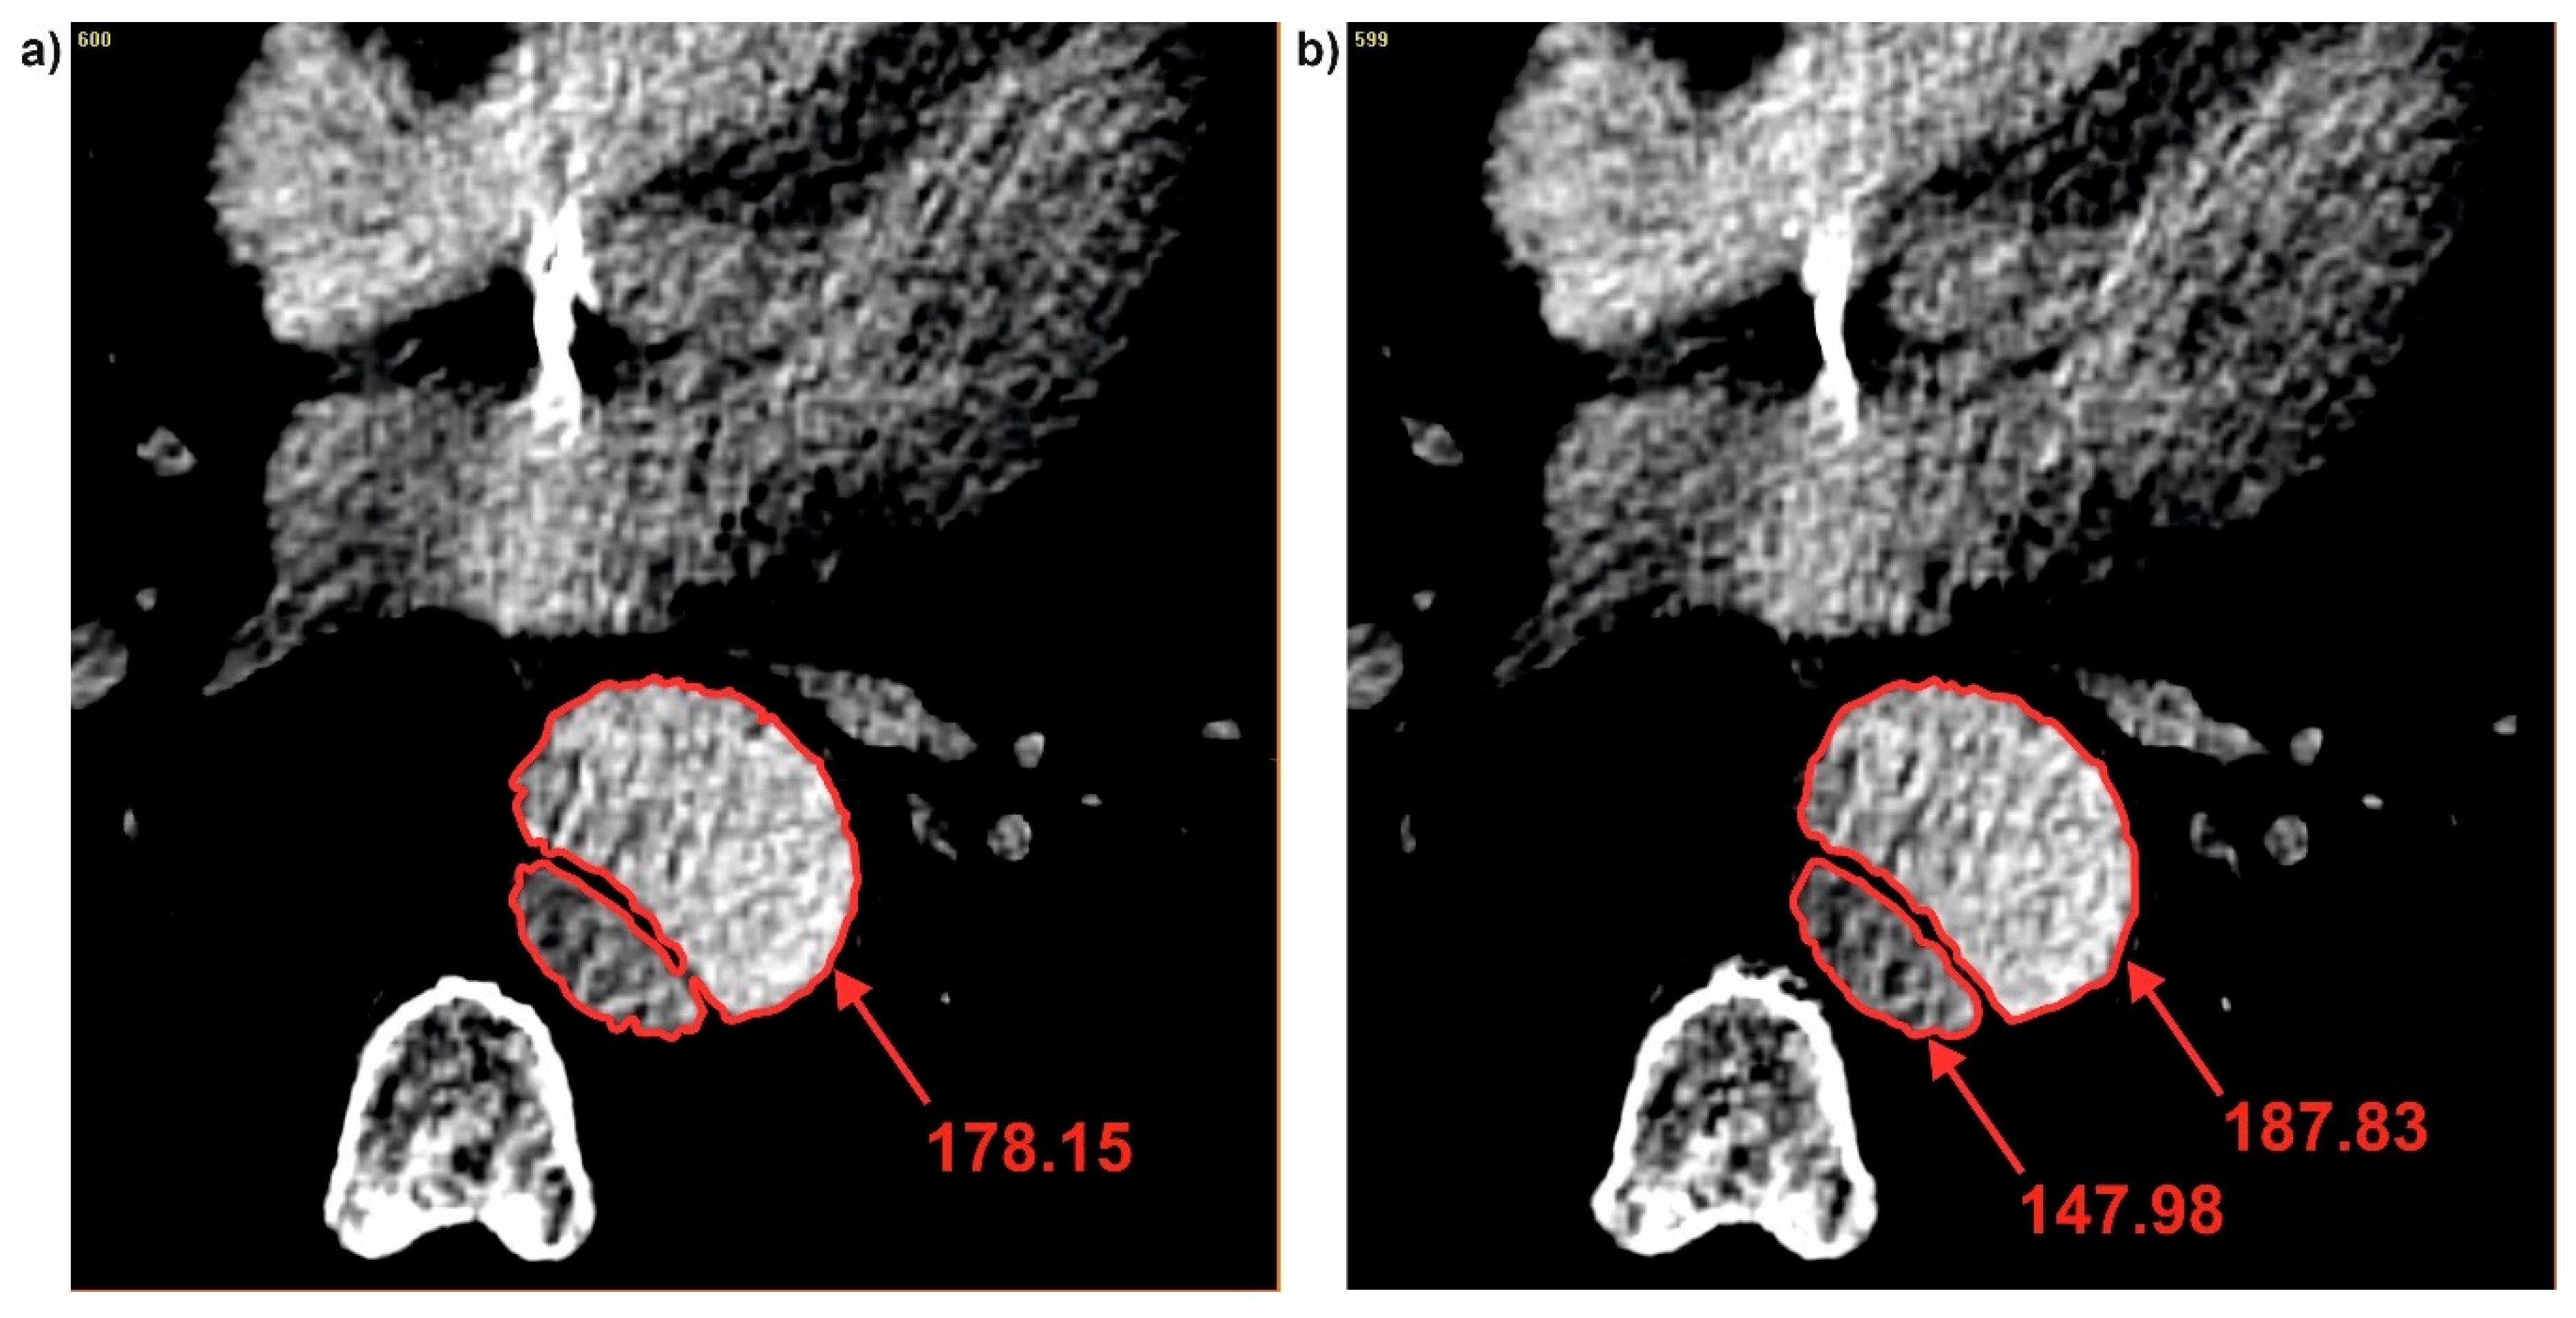

It was also observed that each time when dissection appeared, brightness value in the true lumen was smaller compare to the common duct. While, brightness value calculated for the false lumen each time was higher compare to the common duct. For P1 when the common duct was divided into true and false (for cross-section 96 and 97) brightness value was changed from 178.15 (common duct) (Figure 8a) into 147.98 (true lumen) and 187.83 (false lumen) (Figure 8b). While, for the case when connection of the true and false duct appeared, brightness value between true and false lumen was observed. For P1 when true and false duct created common duct (for cross-section 115 and 116) brightness value was changed from 124.97 (true duct) and 176.57 (false duct) (Figure 9a) into 154.89 (common duct) (Figure 9b).

Figure 8. Brightness changes during channel division: (a) Common duct and (b) true and false duct. Values of brightness were calculated in pixels.